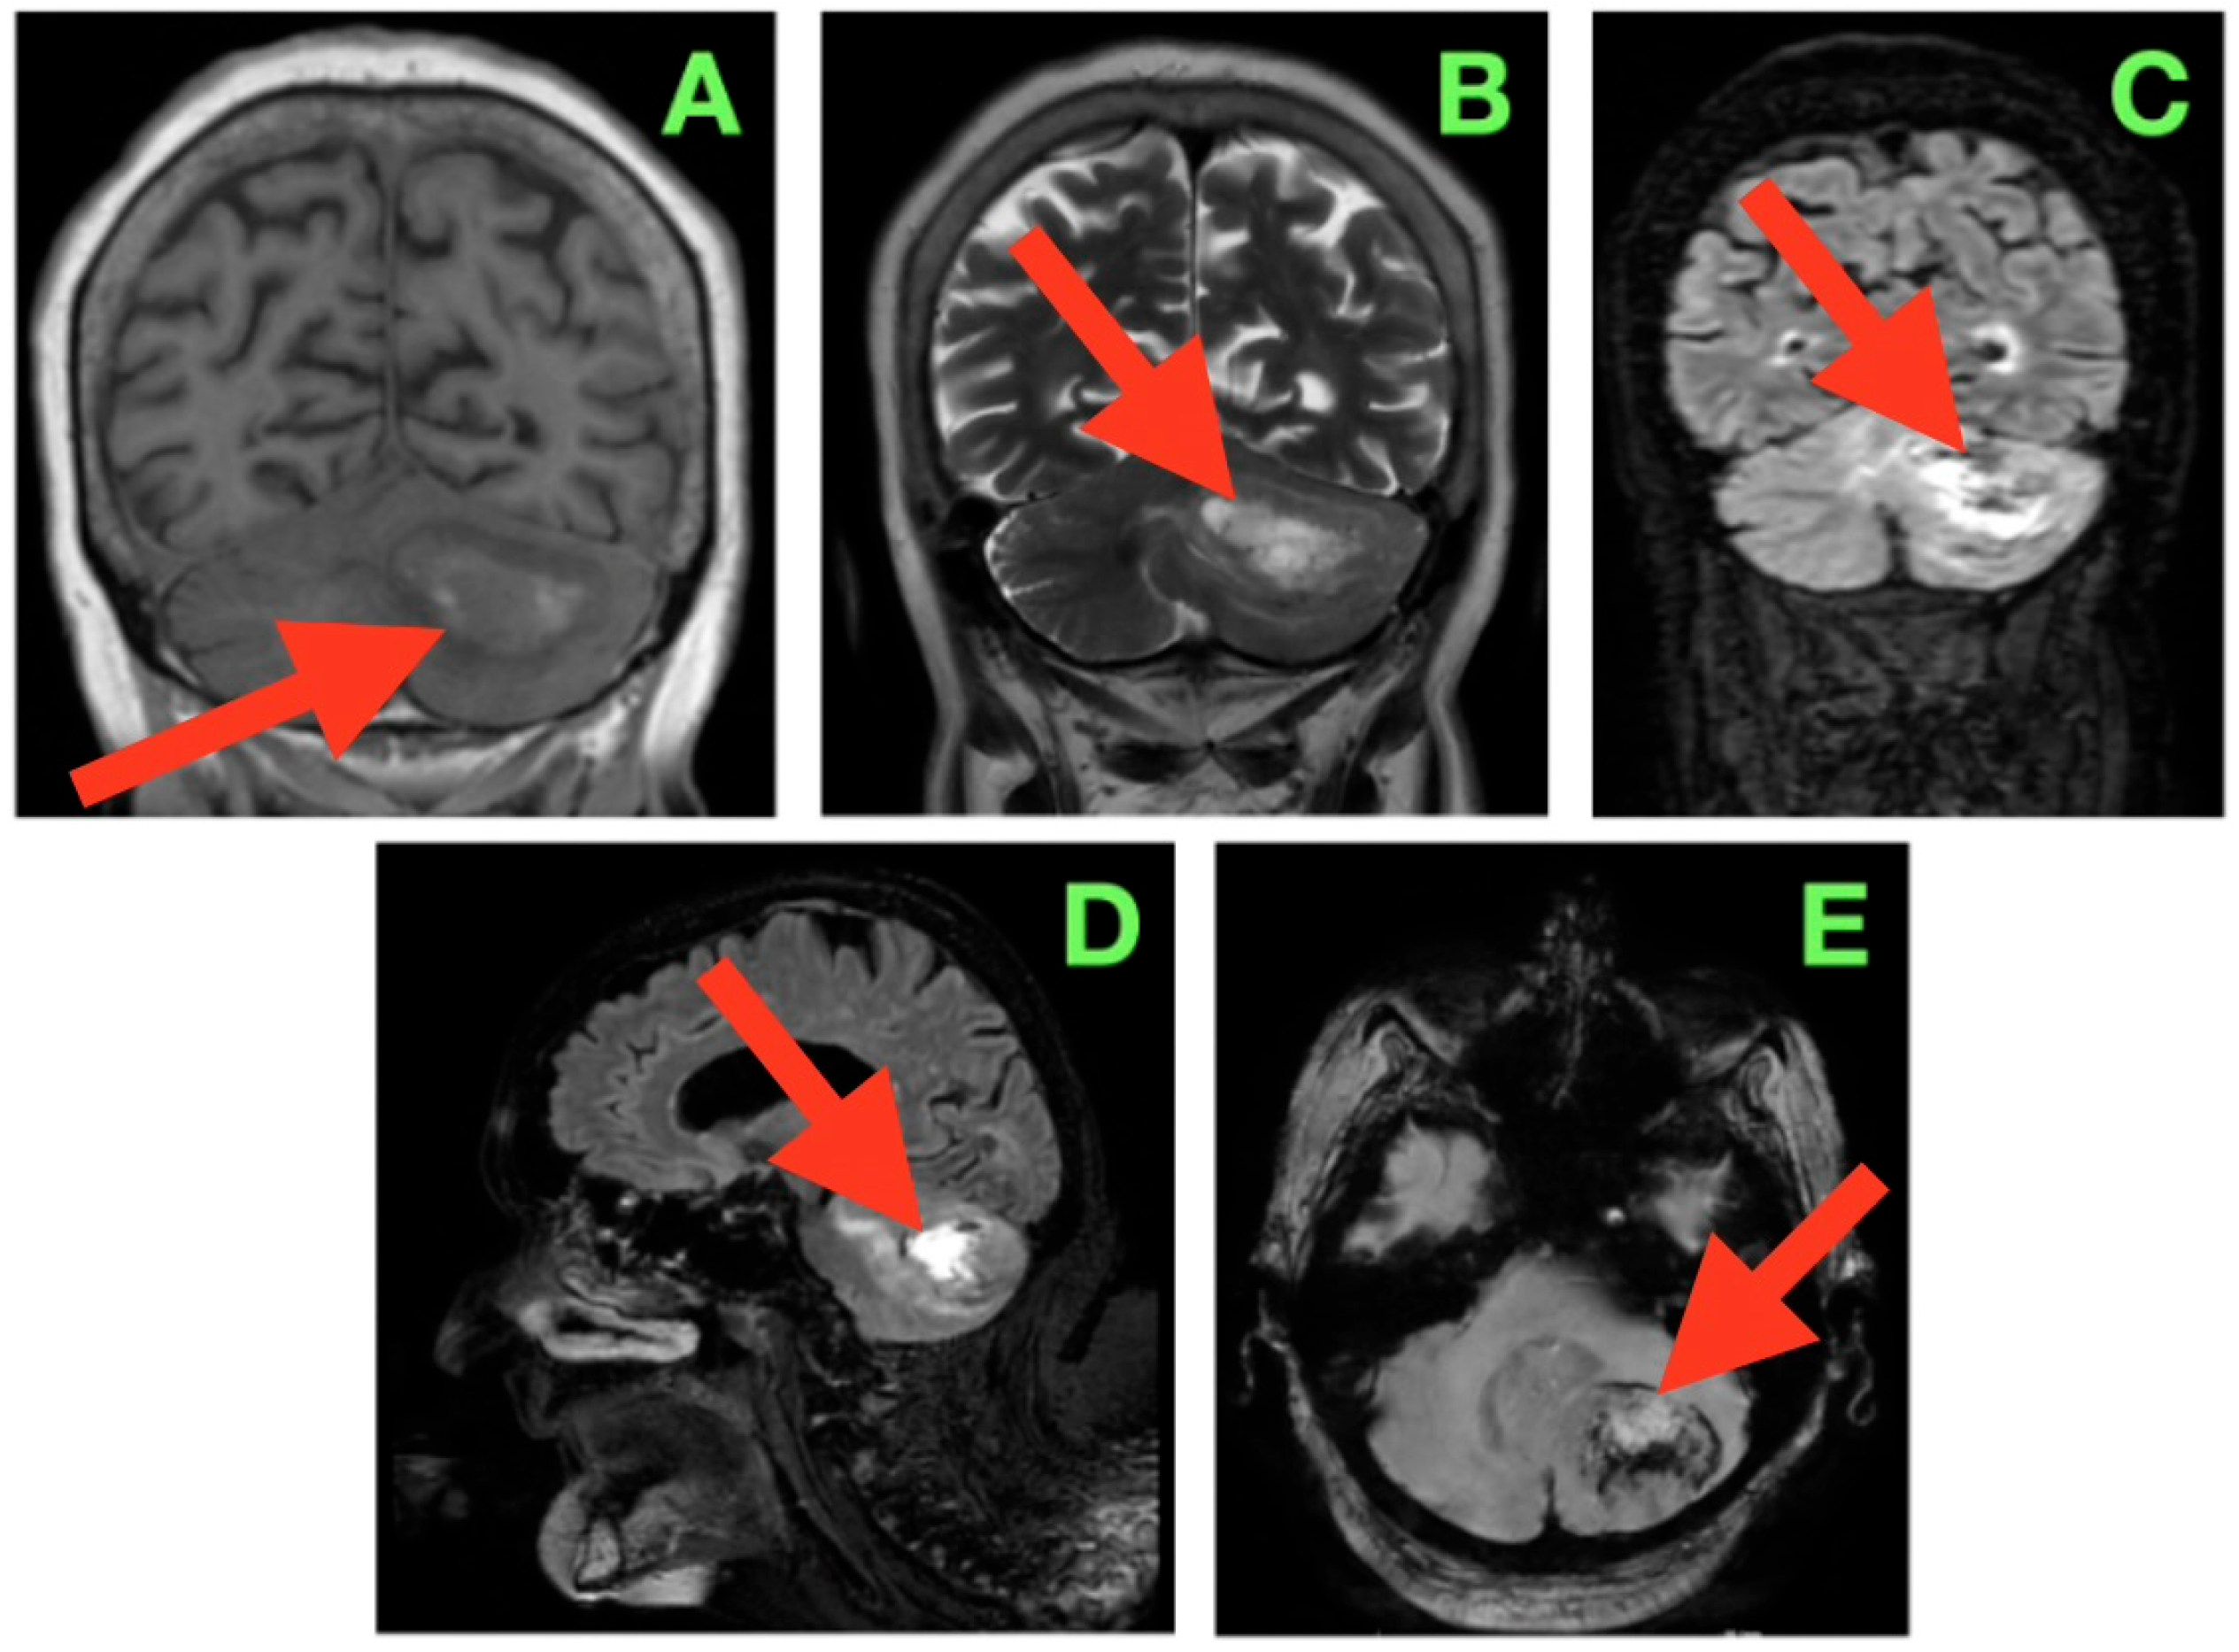

2. Case Presentation